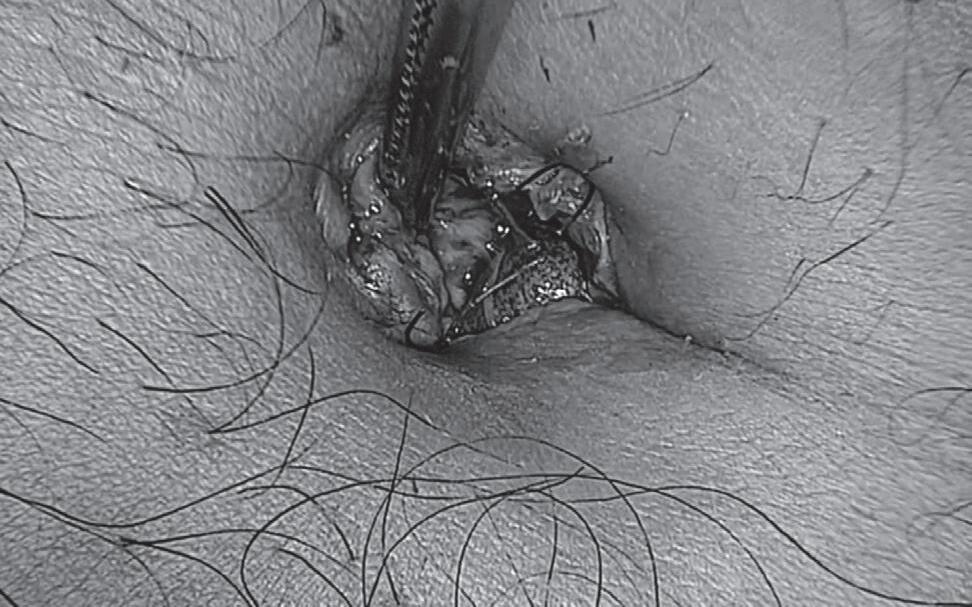

A Figura 1.1 mostra um caso acompanhado no Ambulatório de Ginecologia para Sobreviventes de Câncer do Instituto de Medicina Integral Professor Fernando Figueira. A paciente estava em curso de quimioterapia com 5-FU e leucovorin quando apresentou queixa de dispareunia e conteúdo vaginal abundante, aquoso, amarelado, sem odor e com raios de sangue, sendo diagnosticada com MG associada à quimioterapia com 5-FU. Foi prescrito tratamento tópico com duchas vaginais de benzidamina uma vez ao dia por duas semanas e aplicações de creme vaginal de estriol diariamente por duas semanas; após esse período, 3×/semana. A paciente retornou para consulta de acompanhamento após oito semanas, quando relatou melhora completa dos sintomas.

Figura 1.1 (A e B) Vulva antes do tratamento (A) e após tratamento local com estriol e benzidamina (B) Fonte: imagem pertencente ao acervo da autora Nathalia Ramalho, reproduzida com autorização da paciente.